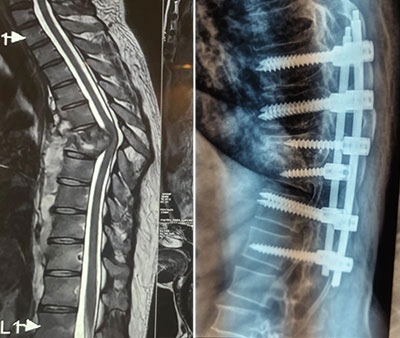

Spinal Fractures & Trauma

Spinal fractures can result from high-impact accidents, falls, or sports injuries, and in severe cases, may lead to nerve damage or paralysis. We are expert in the management of spinal trauma, providing both non-surgical and surgical solutions to stabilize the spine, alleviate pain, and protect spinal cord function. Depending on the type and severity of the injury, treatment options may include spinal fusion, vertebroplasty, or kyphoplasty to restore spinal stability and alignment. Our personalized approach ensures that each patient receives the most appropriate treatment for their condition, promoting optimal recovery.

Spinal Tuberculosis

Spinal Tuberculosis, or Pott’s Disease, is a severe form of tuberculosis that affects the spine, leading to vertebral destruction, spinal deformity, and neurological deficits. We are skilled in diagnosing and treating this rare yet debilitating condition. Treatment typically involves a combination of anti-tubercular medication and, in more advanced cases, surgical intervention to stabilize the spine and prevent further damage. Surgery may include decompression of the spinal cord, abscess drainage, and spinal reconstruction to prevent or correct deformities such as kyphosis.

Kyphosis

Kyphosis refers to an excessive forward curvature of the upper spine, often resulting in a hunched or rounded back. It can be caused by poor posture (postural kyphosis), structural problems with the spine (Scheuermann’s kyphosis), or spinal fractures (especially due to osteoporosis) or congenital.

2. Surgical Treatment:

• Spinal Fusion Surgery: For severe kyphosis (typically greater than 70 degrees), surgery may be needed to correct the curvature and stabilize the spine. This is generally recommended when kyphosis is causing significant pain or affecting lung function.